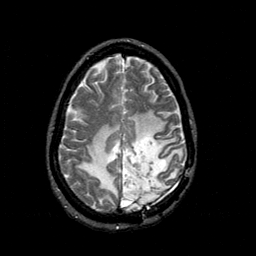

MR Study #1 -- Slice #38